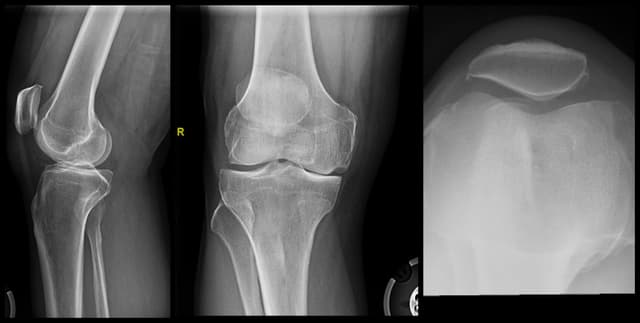

Imaging